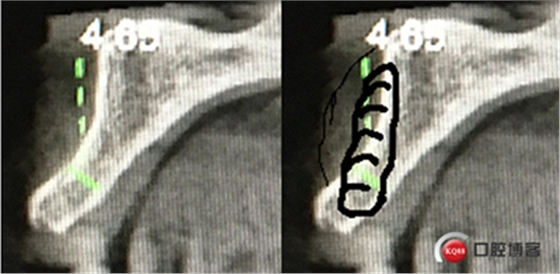

“以修復為導向”,在前牙種植體中心點就是未來牙冠舌側(cè)窩位置。那這個病例植體的方向和位置就只能是下圖右側(cè)這樣了。很明顯植體根尖部分要穿出唇側(cè)倒凹的。怎么辦?翻大瓣植骨蓋膜減張縫合?不!可以不翻瓣,大家仔細看看下圖右圖我畫的那條細細的弧線,是不是跟原來唇側(cè)凹陷的骨面成為左右對稱的兩條弧,也就是說骨膜從原來唇側(cè)凹陷骨面上剝離然后放到左側(cè)我畫的那條弧線那里根本不需要減張,這兩條弧線之間也就是唇側(cè)凹陷處放上骨粉,骨膜不會增加張力。不知道大家看明白了沒有。